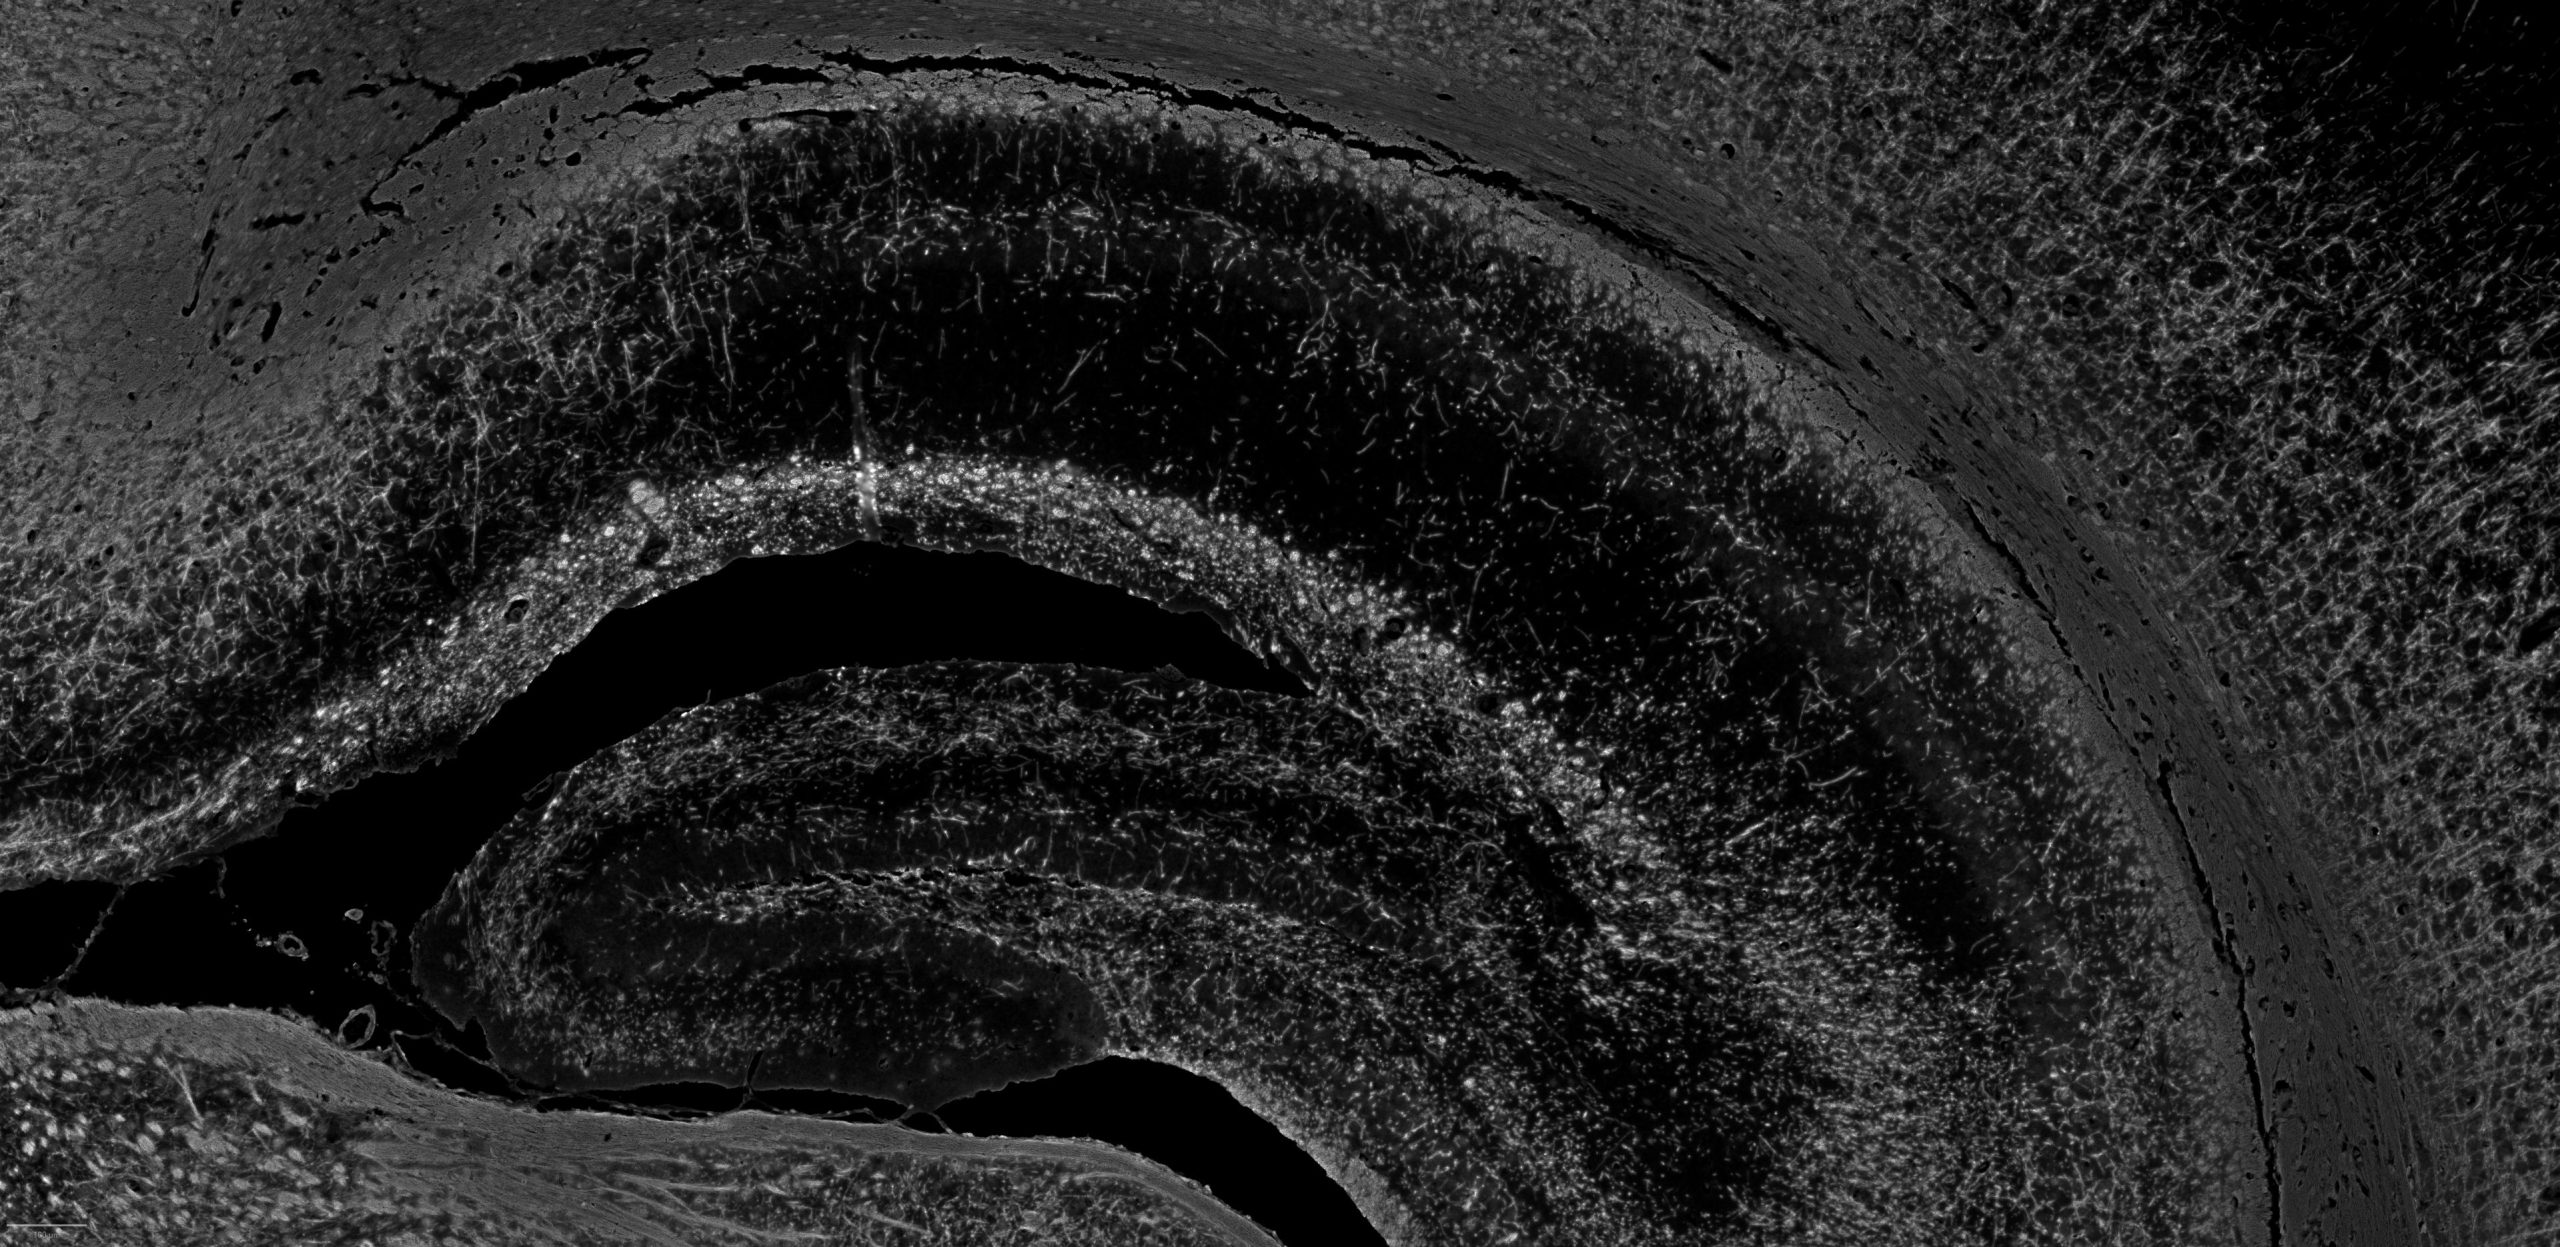

FFPE mouse brain stained with CFP assay

DAPI

NeuN

GFAP

CALB2

Olig2

MBP

CD31

S100b

TMEM119

Iba1

SMMHC